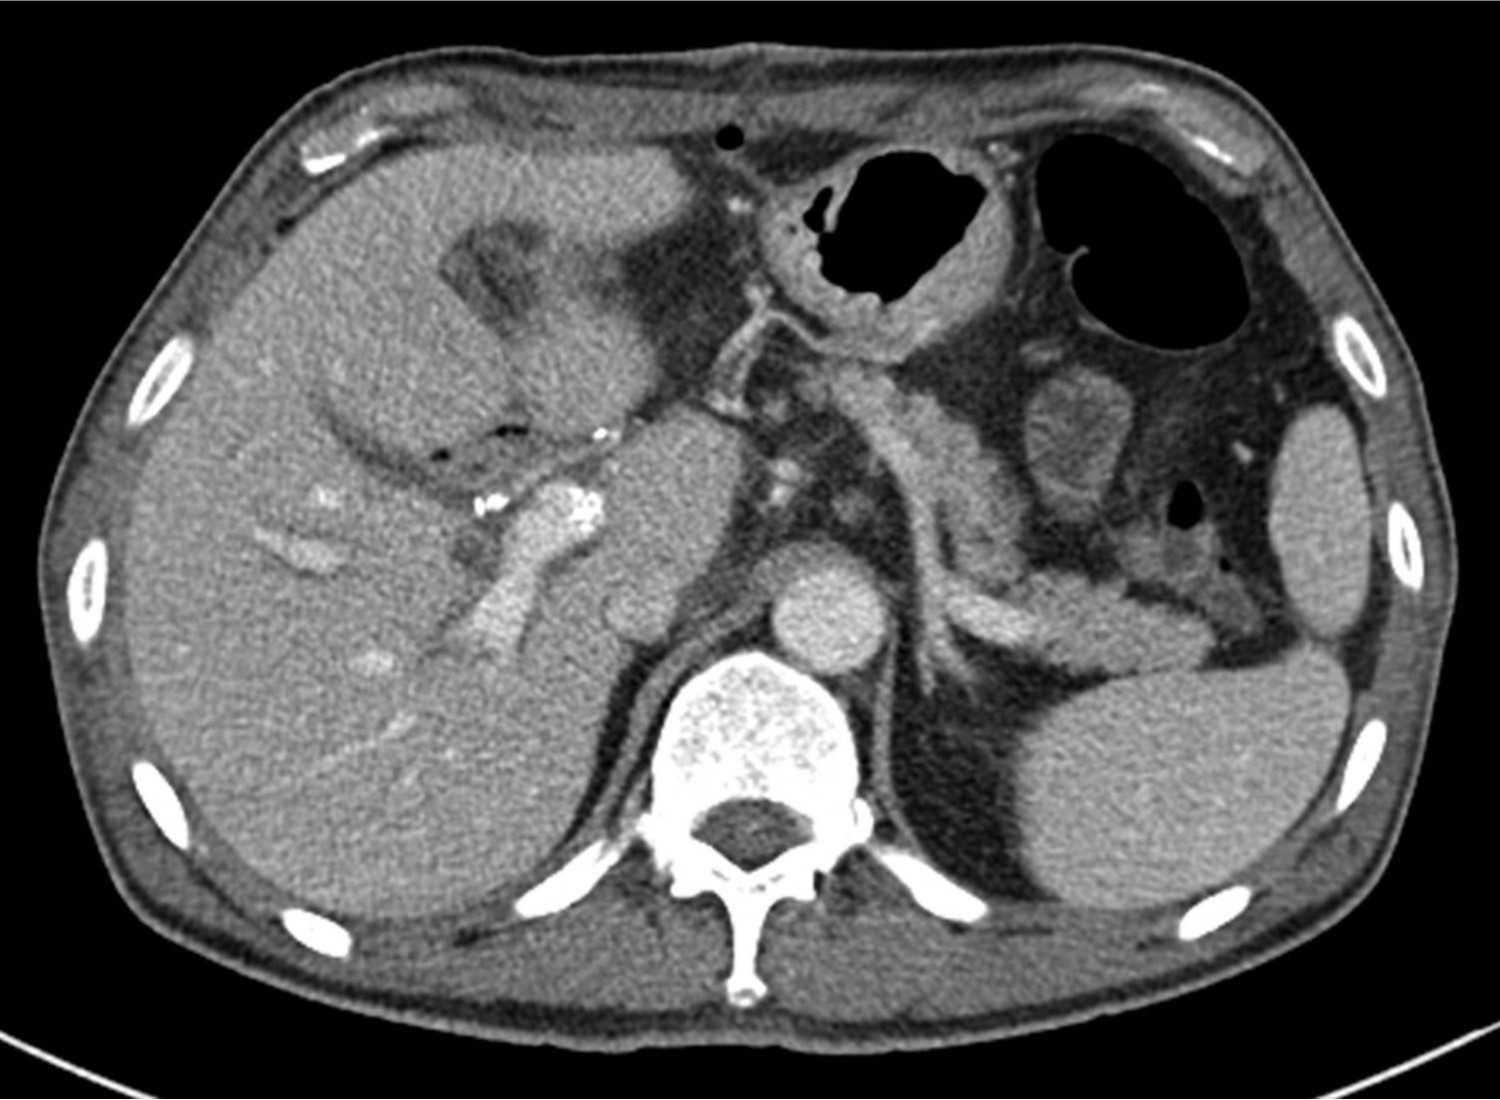

초음파 유도하에 간우엽 S6 담관을 천자하여 5Fr sheath(Terumo, Tokyo, Japan)를 삽입하고 5Fr KMP catheter(Cook, Bloomington, IN, USA)를 상장간막정맥에 위치시키고 시행한 직접 문맥조영술에서 주문맥에 부분적으로 폐쇄가 관찰되었고(Fig. 2a) 혈전으로 인한 폐쇄로 생각이 되었다. 7F McNamara sheath(Cook, Bloomington, IN, USA)를 삽입하여 흡인 혈전제거술을 수차례 시행하여 소량의 혈전이 흡인되었으나 문맥 혈류는 여전히 막혀있었음. 이에 12mm balloon(EverCross, EV3, Plymouth, MN, USA)으로 경피혈관확장술을 시행하였으나 이후 시행한 문맥조영술에서도 문맥 폐쇄 소견은 여전히 보였음. 이어 주문맥에 14x40mm 자가팽창형금속 스텐트(ELuminexx, Bard, Tempe, AZ, USA)를 설치하였으나 문맥에 폐쇄된 분절을 전부 포함할 수 없어 근위부에 12x4cm의 자가팽창형금속 스텐트(Zilver, Cook, Bloomington, IN, USA)를 추가로 설치하고 이후 12mm balloon으로 혈관확장술을 시행하였음. 마지막으로 시행한 문맥조영술에서 문맥은 개통되어 혈류는 회복되었으나 문맥 원위부에는 혈전이 일부 남아있었음(Fig. 2b). 천자한 통로는 histoacryl로 색전후 시술을 종료하였음. 간문맥 스텐트 설치 후 5일 뒤 시행한 CT에서 문맥 스텐트는 개통되어 있었고 조영 후 사진에서 문맥 혈류가 말초까지 가는 것을 확인할 수 있었음(Fig. 3). 환자는 이후 간기능 부전 및 문맥 고혈압의 증상 및 소견 없이 회복하여 퇴원하여 외래 추적 관찰 중임.

Fig. 1. B

Figure 1. Contrast-enhanced CT scan following segmental resection of bile duct with Roux-en-Y hepaticojejunostomy and segmental resection of portal vein with end-to-end anastomosis. Both axial (A) and coronal (B) studies show a thrombus (arrows) in the narrowed main portal vein and peripheral portal flow is not seen.